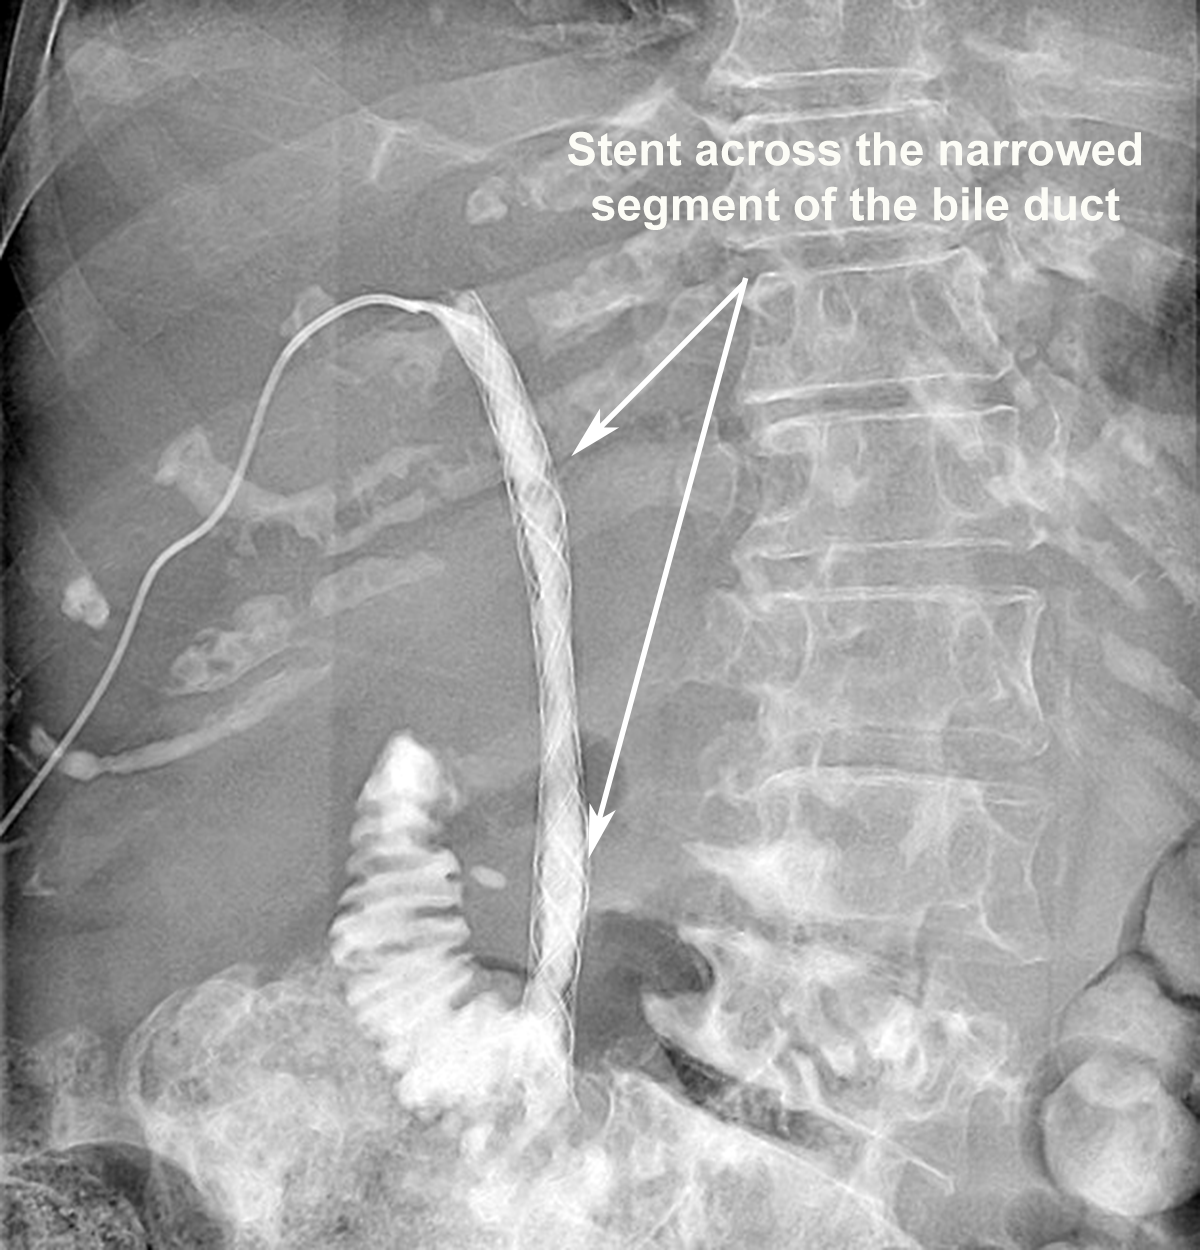

Cancer arising originally from the liver or spread to the liver from cancer elsewhere can cause obstruction to the normal flow of digestive juice (bile) from liver into the bowel. Usually, patients are known to have a cancer or occasionally present to their doctor with symptoms related to this for the first time.

Usually, patients may present with worsening jaundice (yellowing of the white part of the eyes), itching, dark urine and pale/white stools and also sometimes with abdominal pain. The symptoms will worsen and impact on the quality of life if the obstruction is not relieved.

If you or family members have advanced cancer of the liver, which is causing worsening jaundice, this may be treatable with stenting the bile tube/duct which can reduce the yellowish skin discoloration and intractable itching. This may significantly improve the quality of life. Please ask your doctor for relevant information.